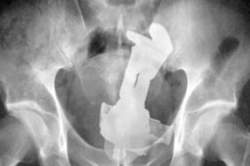

直腸内に長さ20センチ砲弾「自分で入れた」男性、仏病院が治療

>直腸内に長さ20センチ砲弾「自分で入れた」男性、仏病院が治療

直径はどのくらいだったのだろうか